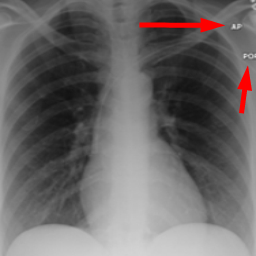

Research is based on the second update of the "COVID-19 Radiography Database" Chowdhury et al. (2020); Rahman et al. (2021); Cov (2022) developed by a team of researchers from Qatar University, Doha, Qatar, and the University of Dhaka, Bangladesh along with their collaborators from Pakistan and Malaysia in collaboration with medical doctors. The database incorporates posterior-to-anterior (AP)/anterior-to-posterior (PA) chest X-ray images from multiple public sources Vayá et al. (2020); Winther et al. (2020); SIR (2020); Cohen et al. (2020a, b); Haghanifar et al. (2022); RSN (2018); Kermany et al. (2018) and contains: 3616 images of COVID-19-positive cases, 6012 images of lung opacity (non-COVID lung infection), 1345 images of viral pneumonia, 10192 images of healthy lungs. Images are provided after conversion to common PNG format with 256x256 dimensions. For each image, the dataset authors provided a corresponding lung segmentation mask obtained using a dedicated U-Net model Rahman et al. (2021). Sample images from the database are presented in Fig. 2.

Many images in the dataset contain annotations or marks made during the image acquisition or afterwards by a radiologist. Examples of such images are presented in Fig. 3. Such symbols in the training dataset are known to generate biases as classifiers tend to target their attention to the presence of the symbols instead of genuine features of the image Rajaraman and Antani (2020); DeGrave et al. (2021). Therefore after the initial preprocessing, consisting of cropping and resizing all images containing such elements were removed.